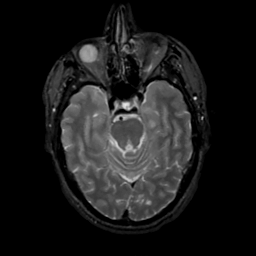

MR Study #8, March 31, 1991 -- Slice #17

[Home][Help][Clinical][Tour 1][Tour 2] Slice 17